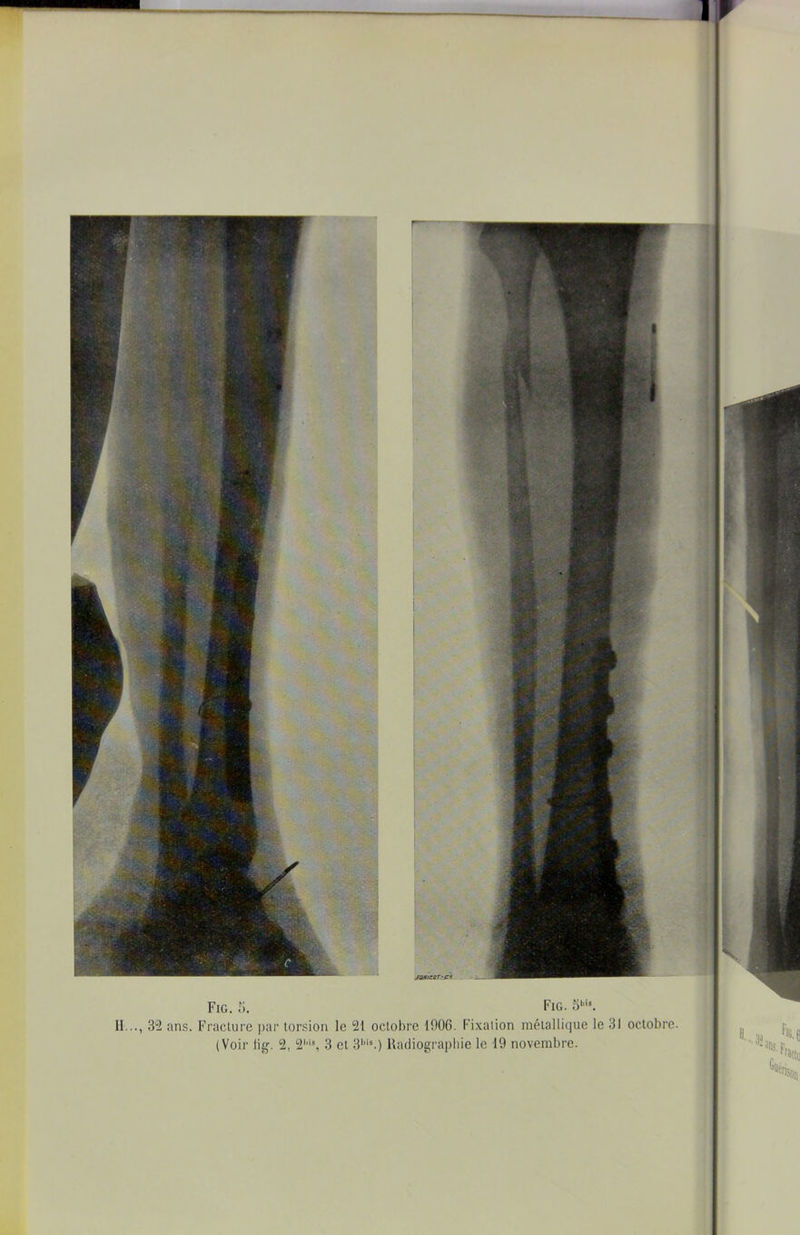

Du traitement des fractures obliques de la jambe / par L. Desguin.

Credit: Du traitement des fractures obliques de la jambe / par L. Desguin. Source: Wellcome Collection.